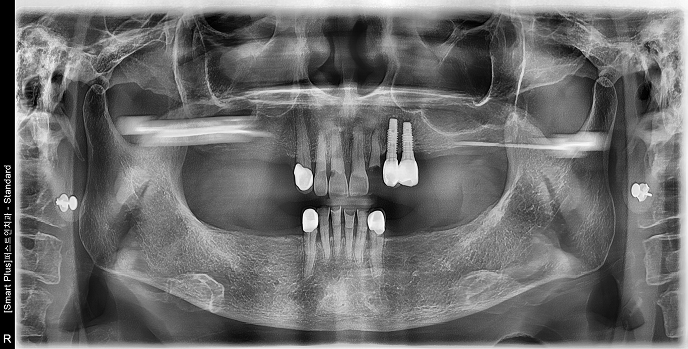

• 70대 남성 | 치주염 | 임플란트 | 치료기간 4개월

Before 2024.12.06

After 2025.04.11